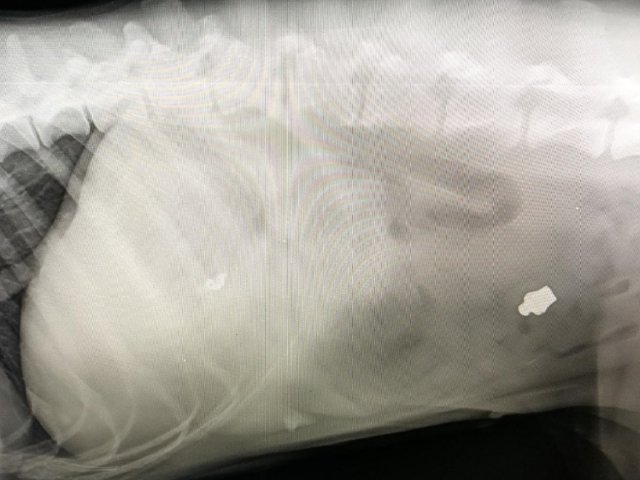

Lineární cizí těleso u 11měsíčního ridgebacka - z rozkousané bundy se zipem a plastového předmětu se vytvořilo lineární cizí těleso bezprostředně ohrožující život, které se na jednom konci zachytilo v žaludku a na druhý konec se navlékla cca 1/2 tenkého střeva. Za ní se bohužel vytvořila tzv invaginace - vchlípení jednoho úseku tenkého střeva do druhého. Kovový jezdec, který byl velmi dobře patrný na rentgenu, byl paradoxně volně v tlustém střevě a nezpůsoboval významnější obtíže. Museli jsme na několika místech vstoupit do žaludku a střev, přerušit a vyjmout cizí těleso, uvolnit vchlípení, zrevidovat životaschopnost střev a po zhodnocení stavu a perfuze krví uvést vše do původního stavu a dutinu břišní po výplachu uzavřít. Pacientovi se daří dobře, střeva fungují a už sám přijímá potravu.